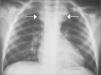

Asociada a esta malformación aórtica se observó la presencia de una vena innominada izquierda que seguía un trayecto anómalo, cruzando el mediastino de izquierda a derecha por delante de la carina y posterior a la aorta torácica ascendente, para alcanzar la vena cava superior (fig. 2).